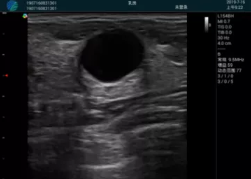

M20查看:囊內(nèi)回聲均勻,邊界清晰,囊壁光滑

M20引導(dǎo)抽吸術(shù)后囊腫消失,原區(qū)域空腔形成,脂肪層與腺體層架構(gòu)發(fā)生改變